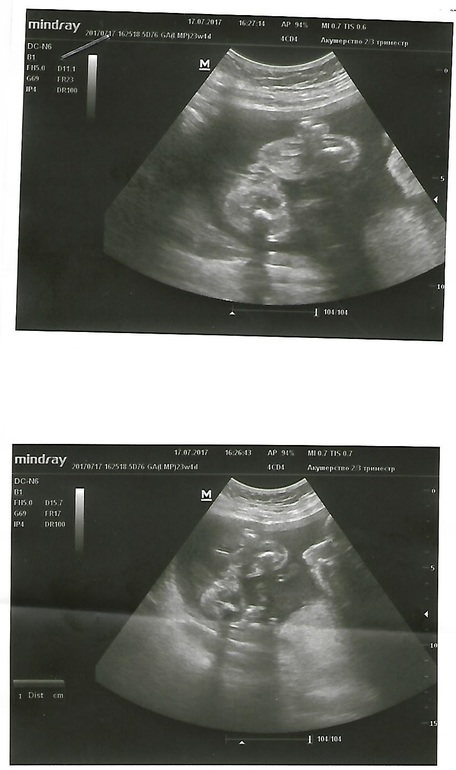

Пол малышаКак же я мечтала о мальчике, но нет, сегодня я пошла на узи только за определением пола и больше ничего не смотрели и итог всё таки там ОНА

Да ну и фото Вам покажу для наглядности